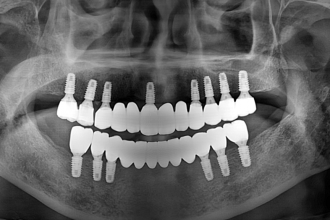

임플란트